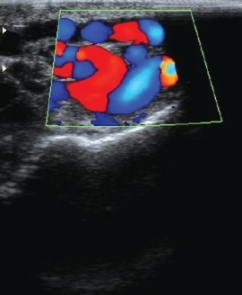

What's the Diagnosis?